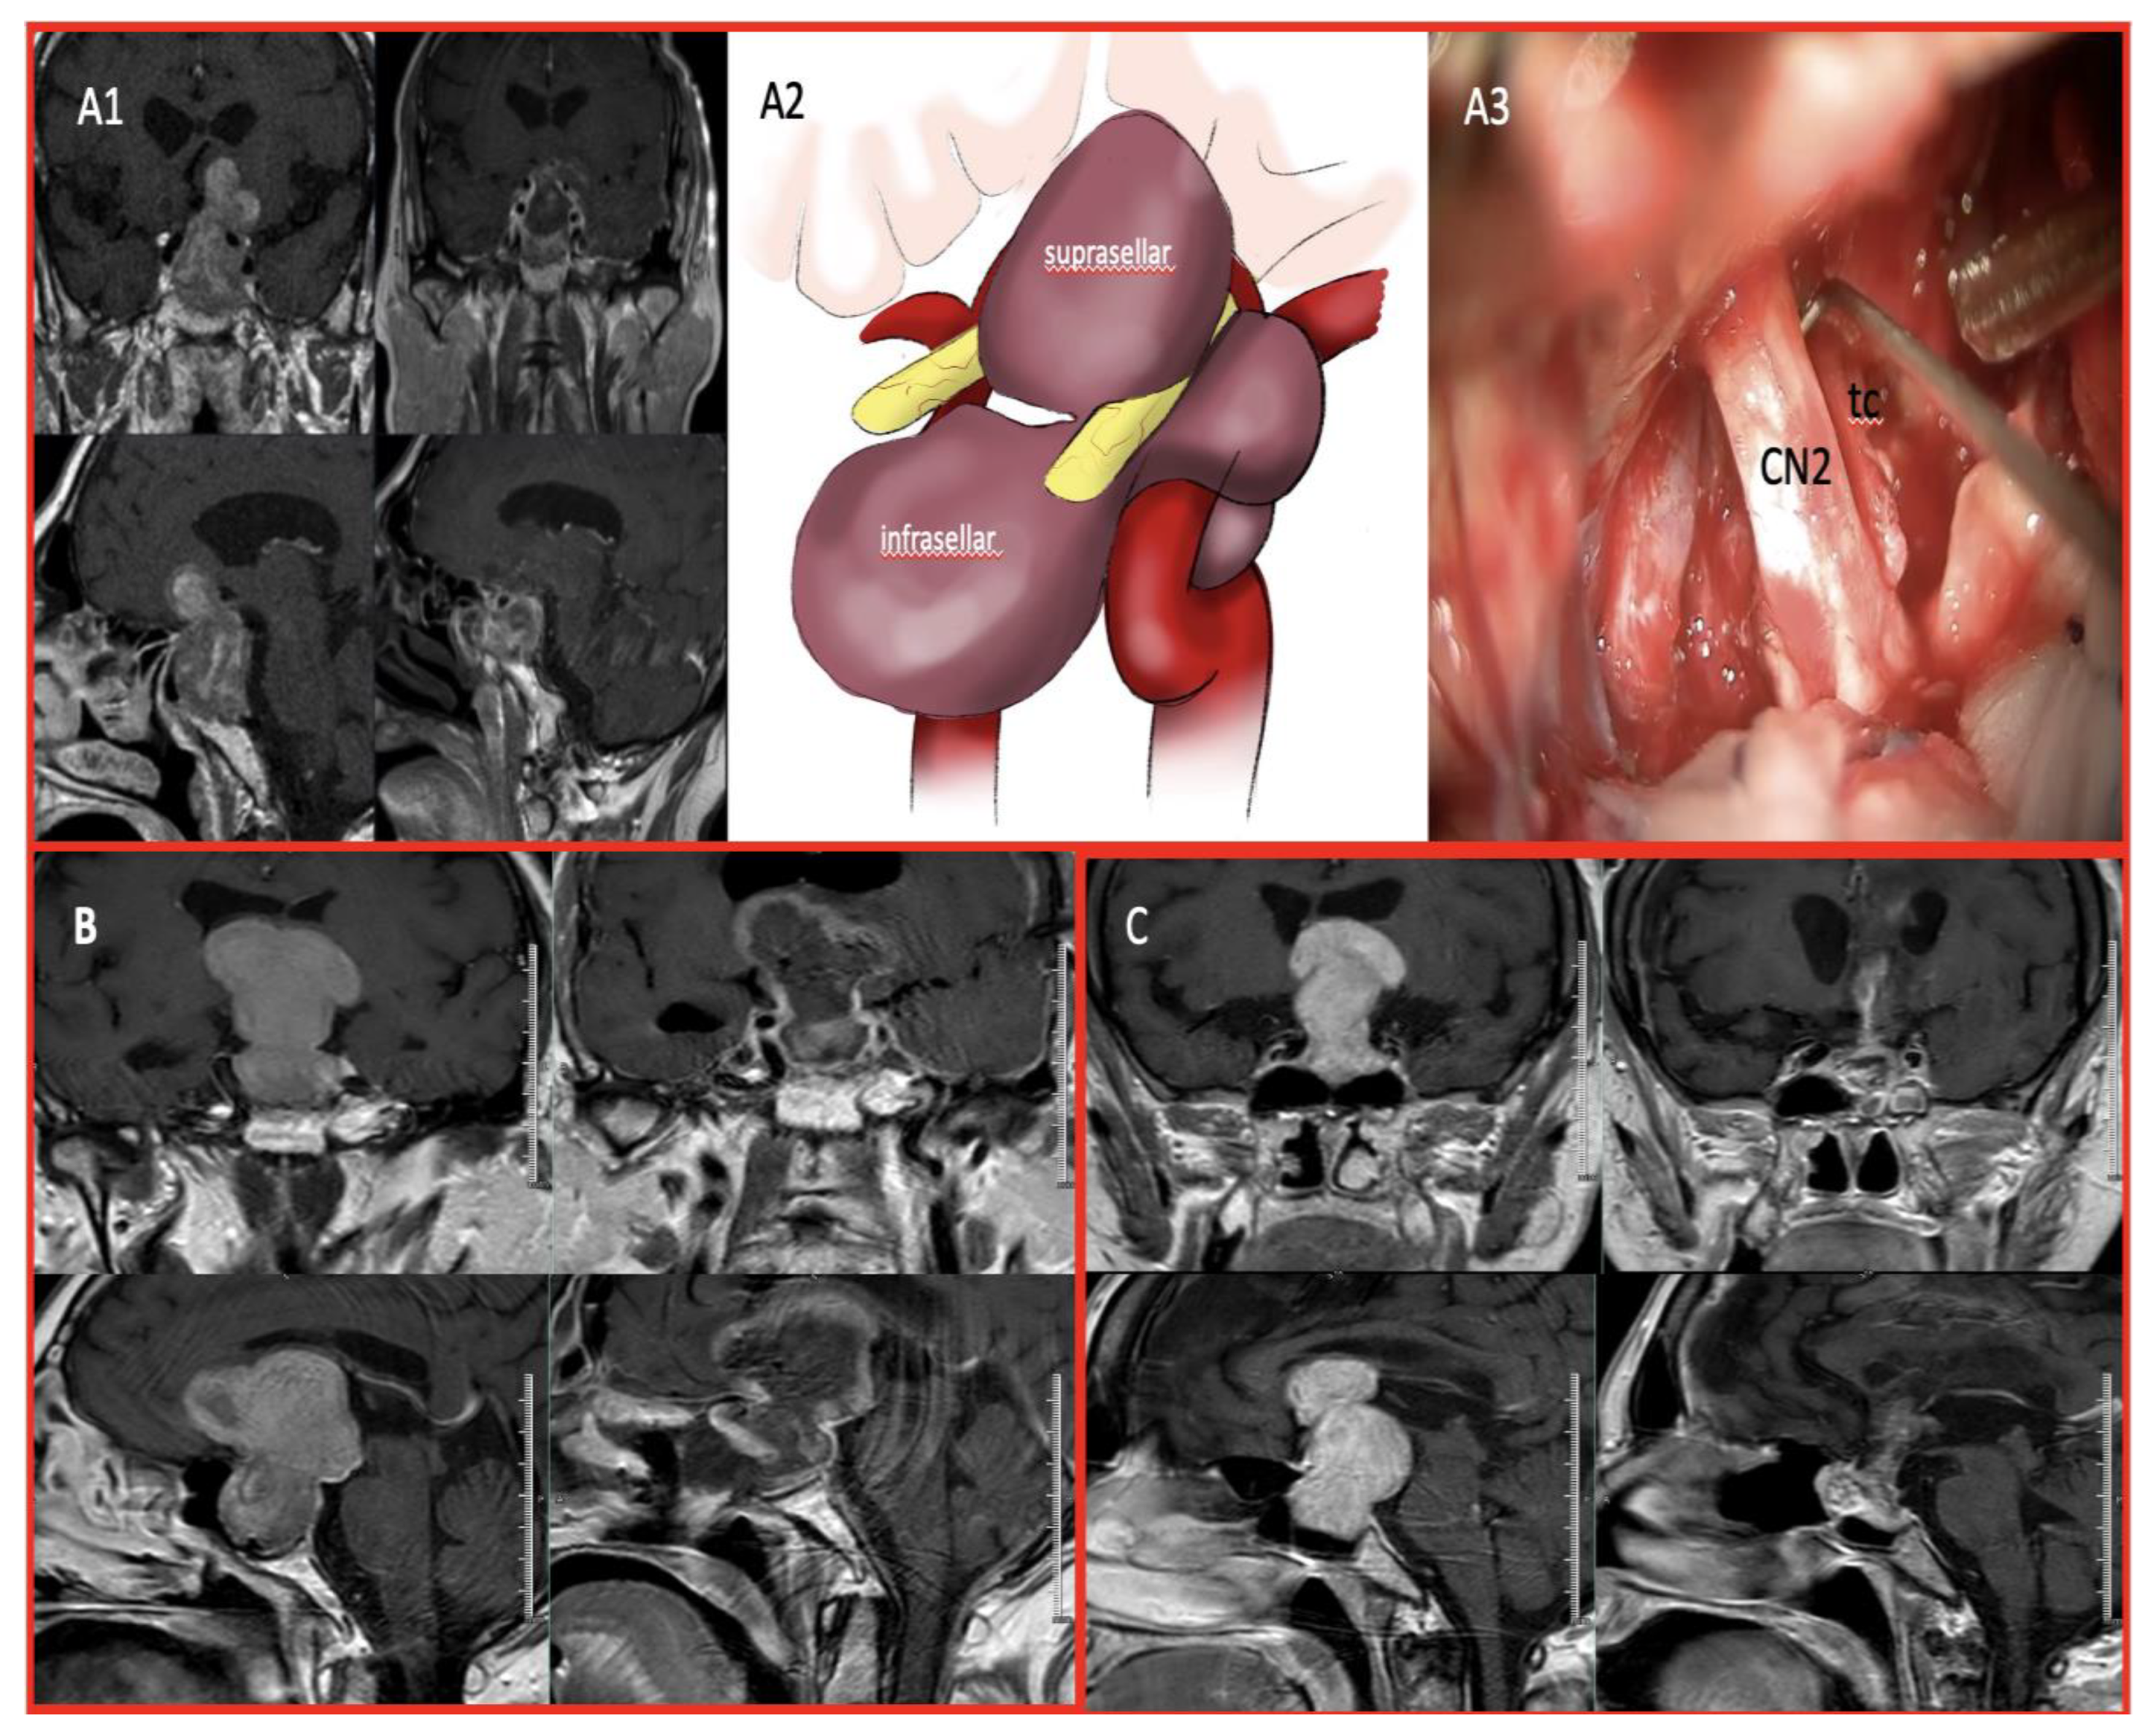

For Zone 3 and complex tumors, an additional transcranial approach was employed in selected cases. Tumors extending into the anterior skull base, temporal lobe, or lateral ventricle were managed using simultaneous or staged frontotemporal, transcallosal or pterional craniotomy combined with endoscopic surgery.(Figure 2) Following the dural opening, meticulous microsurgical dissection was performed to separate the tumor from the optic apparatus, major vascular structures, and surrounding brain parenchyma. Internal debulking was performed using ultrasonic aspiration or suction, facilitating safer capsular dissection.

Figure 2. A1. Preoperative MRI of a Zone 3 multilobular-shaped tumor and postoperative MRI following near-total resection using a combined approach. A2. Illustrative representation of the anatomical extension way of a giant adenoma. A3. Demonstration of the close relationship between optic nerve and tumor capsule during the transpterional approach. B. Preoperative MRI of GA extending into the frontal lobe and lateral ventricle, and postoperative MRI following NTR using a combined approach.(EEA+Transpterional) C. Preoperative MRI of GA extending into lateral ventricle, and postoperative MRI following NTR using a combined approach.(EEA+Transcallosal).